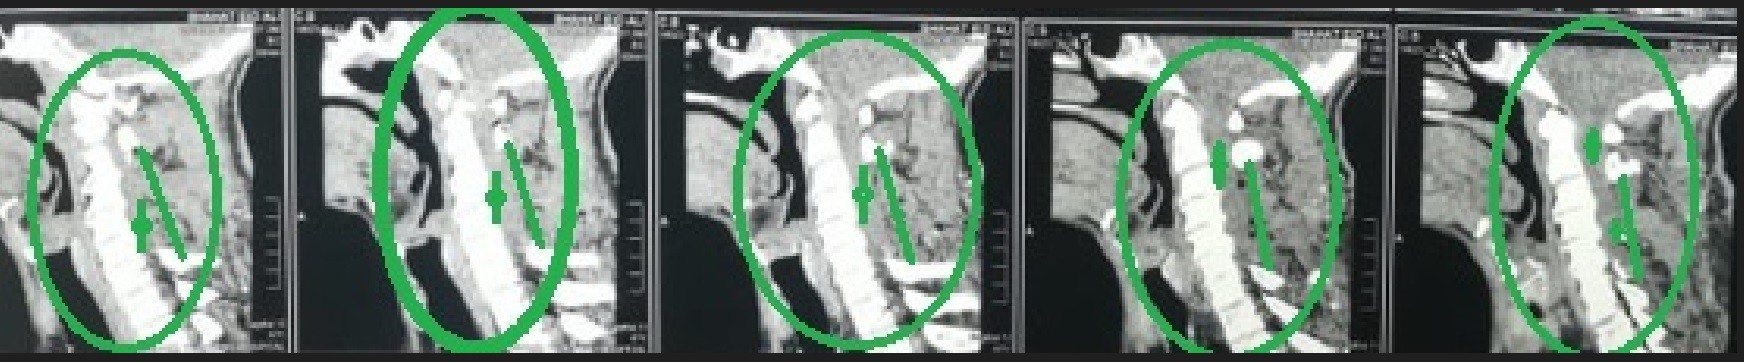

A successful surgery was performed to decompress a narrowed cervical spinal canal. This condition occurs when the spinal canal in the neck area narrows, causing pressure on the spinal cord and nerves supplying the arms and hands.

• Accurate preoperative planning using advanced imaging